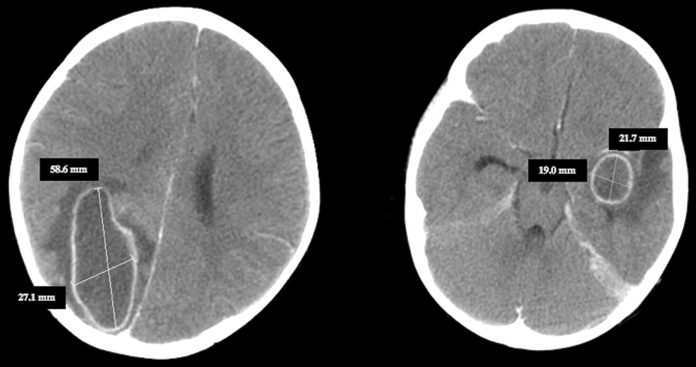

- Αξονική τομογραφία και μαγνητική είναι διαγνωστικές μέθοδοι εκλογής – τα ευρήματα είναι αντίστοιχα με το στάδιο του αποστήματος

Υπάρχουν λίγες εξαιρέσεις σε αυτόν τον κανόνα: Η μηνιγγίτιδα του Haemophilus influenzae σχετίζεται, συχνά, με συλλογές που θεωρούνται λανθασμένα ως υποσκληρίδια εμπυήματα. Αυτές οι συλλογές υποχωρούν με αντιβιοτικά και δεν απαιτούν χειρουργική θεραπεία. Η φυματίωση μπορεί να προκαλέσει αποστήματα εγκεφάλου που μοιάζουν με τα συμβατικά βακτηριακά αποστήματα στην απεικόνιση CT (αξονική τομογραφία). Η χειρουργική αποστράγγιση ή αναρρόφηση είναι συχνά απαραίτητη για τον εντοπισμό του Mycobacterium tuberculosis, αλλά, μόλις γίνει η διάγνωση, δεν απαιτείται περαιτέρω χειρουργική επέμβαση. Η στερεοτακτική αναρρόφηση καθοδηγούμενη από CT υποδεικνύεται, επίσης, στη θεραπεία του εγκεφαλικού αποστήματος.

- Διαδοχικές αξονικές τομογραφίες ή μαγνητικές τομογραφίες για να επιβεβαιώσουν την προοδευτική λύση, πρώιμη ανίχνευση και αντιμετώπιση επιπλοκών